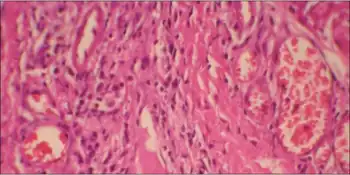

Pathophysiology

In the two predominant mutations of NSML (Y279C and T468M) the mutations cause a loss of catalytic activity of the SHP2 protein (the gene product of the PTPN11 gene), which is a previously unrecognized behavior for this class of mutations.[9] This interferes with growth factor and related signalling. While further research confirms this mechanism,[10][11] additional research is needed to determine how this relates to all of the observed effects of NSML.